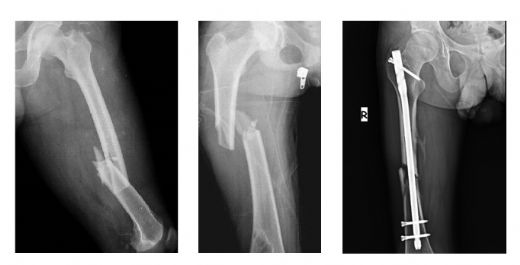

Tanısı Femur kemiği kırığının tanısı, genellikle fiziksel muayene ve görüntüleme yöntemleri ile konulur. Doktor, hastanın şikayetlerini dinledikten sonra aşağıdaki yöntemleri kullanabilir:

Tedavi Yöntemleri Femur kemiği kırığının tedavisi, kırığın tipine, yerine ve hastanın genel sağlık durumuna bağlı olarak değişiklik gösterir. Genel olarak tedavi yöntemleri şunlardır: